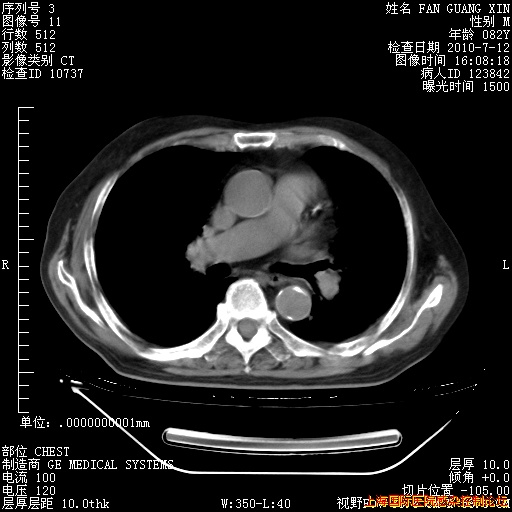

今天复查CT

今天CT

整整相隔30天的肺部CT好像有所好转啊。甲强龙减量第3天,需要观察体温。